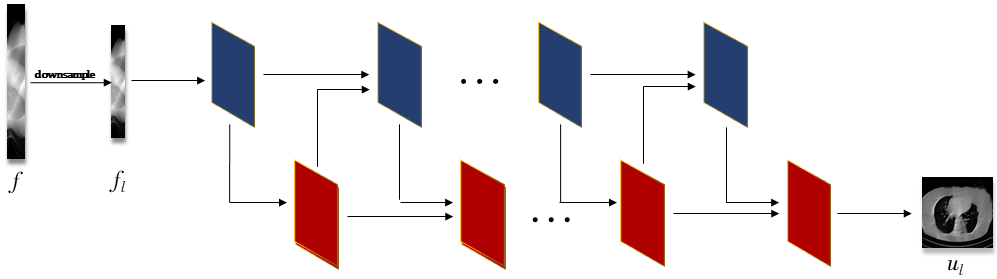

The unrolling strategy is a discriminative learning method by unrolling an iterative optimization algorithm into a hierarchical architecture. Fig. 1 depicts the network structures of low-resolution reconstruction model, we use the classical learned primal-dual reconstruction method [22] to obtain the low-resolution solution , for which we can also adopt other advanced learning-based methods or variational methods. Fig. 2 depicts the network structures of our LRIP-net, which has three inputs including the incomplete projection data , the system matrix , and the reconstructed low-resolution image . More specifically, there are three blocks in each stage of the high-resolution reconstruction, which correspond to the three variables. As shown at the bottom of Fig. 2, each block involves a 3-layer network.